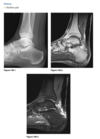

A lateral radiograph of the left foot demonstrates a prominent talar beak

­ (arrow) and bony sclerosis overlying the middle

facet (arrowheads). Coronal CT through the middle

facet shows talocalcaneal fusion, with bony bridging between the talus and the sustentaculum tali of the

calcaneus

Diagnosis: Tarsal coalition

abnormal fusion

of one or more of the tarsal bones, may be fibrous,

cartilaginous, or osseous and may be posttraumatic, or congenital.

Most

common tarsal coalitions are calcaneonavicular and

talocalcaneal.

Radiographically, calcaneonavicular coalition may

be suspected because of elongation of the anterior

facet of the calcaneus on radiographs (i.e., anteater

sign. CT can also be used to confirm coalition and shows

­ sclerosis at the articulation

Congenital coalition usually evolves from fibrous to osseous

coalition and may not be apparent on the initial

evaluation

Talocalcaneal coalition can result in dorsal beaking

of the talar head (Fig. 2.3.6, arrowhead), the so-called

C-sign (arrows)